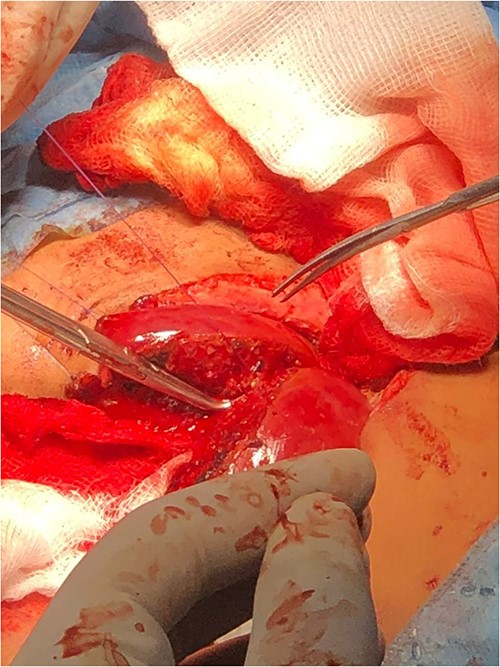

After anesthetic preparation and central line insertion, both twins were placed on sterile sheets and then prepped anteriorly, Incision was made using monopolar and bipolar diathermy in the connecting bridge, skin and muscle were cut, connections within parietal peritoneum were identified, and then carefully divided, followed by the connecting part of the liver (Fig. 2), after two and half hours of surgery the twins were finally separated and other twin was taken to another table.

Connections within parietal peritoneum were identified and then carefully divided, followed by the connecting part of the liver.